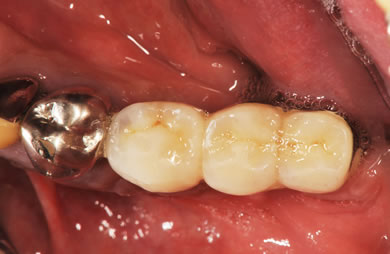

インプラントの症例写真 IMPLANT

スピードインプラント治療+セラミック治療

| 治療内容 | インプラント3本(抜歯即日スピードインプラント)、ハイブリッドセラミック3本 | ||||||||||||||||||||||||||||||||

| 治療期間 | 8ヶ月 |